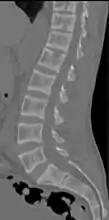

Renal osteodystrophy is usually diagnosed after treatment for end-stage kidney disease begins; however the CKD-MBD starts early in the course of CKD.[1][6] In advanced stages, blood tests will indicate decreased calcium and calcitriol (vitamin D) and increased phosphate, and parathyroid hormone levels. In earlier stages, serum calcium, phosphate levels are normal at the expense of high parathyroid hormone and fibroblast growth factor-23 levels. X-rays will also show bone features of renal osteodystrophy (subperiostic bone resorption, chondrocalcinosis at the knees and pubic symphysis, osteopenia and bone fractures) but may be difficult to differentiate from other conditions. Since the diagnosis of these bone abnormalities cannot be obtained correctly by current clinical, biochemical, and imaging methods (including measurement of bone-mineral density), bone biopsy has been, and still remains, the gold standard analysis for assessing the exact type of renal osteodystrophy.[6][16]